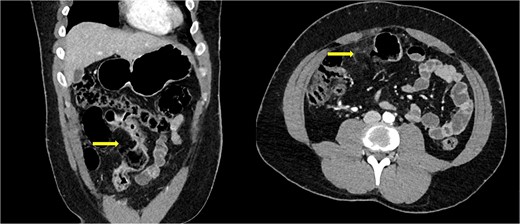

Nine hours after the initial surgical review, the patient became febrile and tachycardic. Inflammatory markers had worsened despite broad-spectrum antibiotics. As a result, he was prepared for an emergency laparotomy. Intraoperatively, we found a small ileal perforation at the mesenteric border, ~30 cm from the ileocaecal junction with overlying attached omentum, sealing off the perforation (Fig. 2). There was no evidence of generalized peritonitis or peritoneal contamination. The rest of the terminal ileum was consistent with Crohn’s disease up to the ileocecal junction.

Photographic imaging showing the site of perforation in the small bowel.